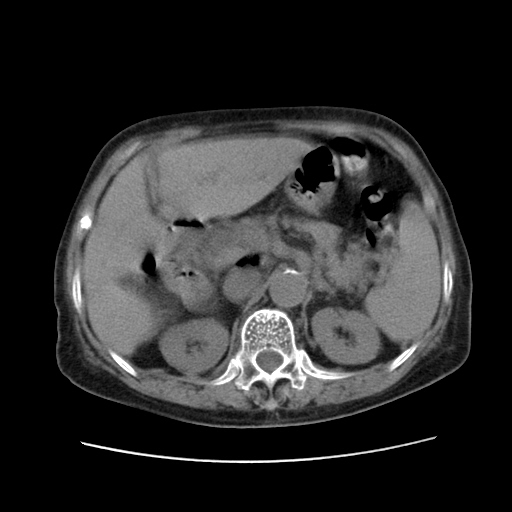

女,77.无不适

胆总管扩张

肝旁多发胆囊状液体影考虑肠腔积液基中部分囊状景不多外胆囊

肝右叶肝内胆管结石并肝内胆管扩张。胆总管下段梗阻,考虑壶腹部占位。

肝右叶肝内胆管结石并肝内胆管扩张。胆总管下段梗阻,考虑壶腹部占位。支持